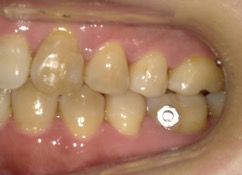

AFTER

30代 女性 叢生 AFTER

上下に叢生が見られる。歯列の拡大、臼歯の遠心移動、IPRを組み合わせてインビザラインで治療を行う事にした。

コンプライアンスが良く、治療に協力的だったため治療はスムーズに進んだ。